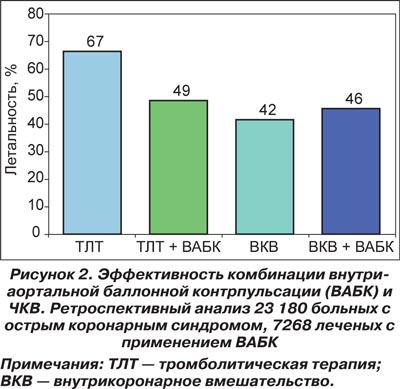

Так, проведение фибринолитической терапии в ранние сроки ОИМ, осложненного развитием КШ, позволяет снизить уровень летальности больных до 67 %, а применение фибринолитиков совместно с баллонной контрпульсацией приводит к положительному исходу более чем у половины больных. Чрескожное коронарное вмешательство (ЧКВ) является методом выбора для лечения этой категории пациентов. Стентирование коронарных артерий позволяет уменьшить летальность этой крайне тяжелой категории пациентов до 42–46 %. При этом результаты лечения значительно меньше зависят от использования методов вспомогательного кровообращения (рис. 2).